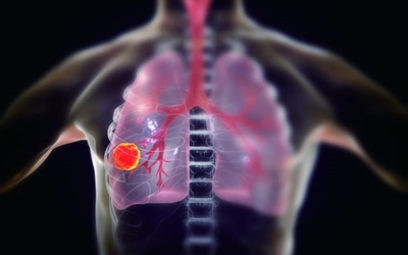

6. 폐암 초기 증상 - 혈담

혈전은 반드시 폐암이 아니어도 나타날 수 있습니다 . 혈담이란 기침 후에 피가 나오 거나 가래에 피가 섞여 있는 것을 혈담 이라고 합니다 . 그러나, 의심스러운 폐암의 초기 증상의 혈담은, 선홍색의 비교적 선명한 피가 나오는 것을 의심해 봐야 합니다 . 이것은 암세포 때문에 폐가 괴사하기 때문 입니다 . 이 경우 폐암 초기보다는 암세포가 확장되었다고 보는 것이 좋습니다 . 폐암 환자의 25% 가 혈담을 했다고 통계가 나온 적이 있습니다 .